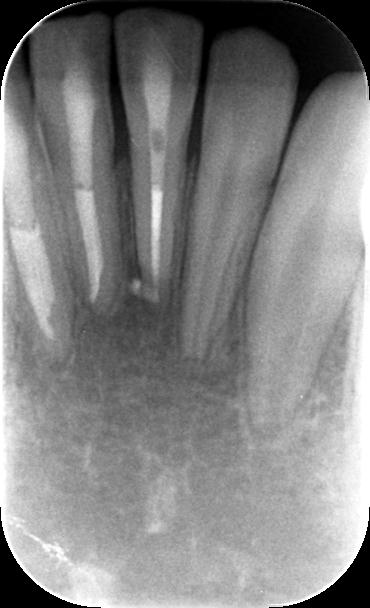

1ヶ月後の経過のレントゲン写真です。歯根の先にみられた透過像が大きくなっているのが確認できます。

また歯の動揺も改善がみられず、積極的に治療をすべきかどうか非常に悩ましい状態でありましたが

歯の神経は歯髄電気診で前回と変わらず生きている検査結果を示しているため今回も経過観察といたしました。